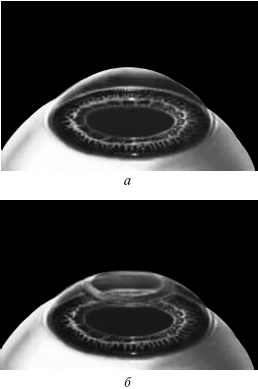

Рис. 9. Форма роговицы до проведения коррекции (а) и после коррекции близорукости (б). Испарение нескольких микрон толщины роговицы привело к уменьшению ее кривизны в центре.

Иллюстрация с сайта Международного лазерного центра www.optics.ru